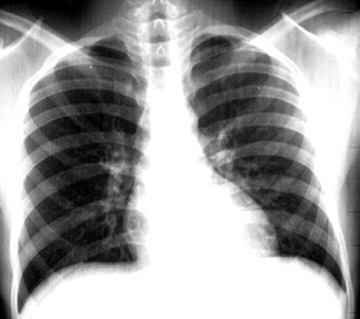

Tuberculosis Spine

Loss of intervertebral space and collapse of vertbra is visible. Click the image on the left to see a close up.